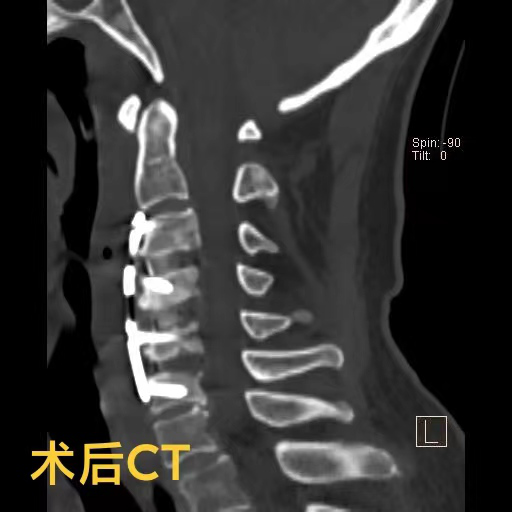

罗医生第一时间联系了神经外科脊柱脊髓组的邓雷主治医师。针对陈爷爷及其家属的担忧,邓雷主治医师进行了耐心细致的沟通,最终陈爷爷决定配合医护进行手术治疗。患者高龄且有基础疾病,手术方案需要慎之又慎。神经外科副主任(主持工作)徐忠烨主任医师组织全科医生根据患者具体病情,制定了最终方案:前路3节段颈椎间盘切除+颈椎后凸畸形矫正。

陈爷爷长期的颈椎变形产生了大量骨质增生,给术中的邓雷、蒋登志医生出了难题。在神经显微镜下,他们的眼睛如鹰,指尖之中飞舞最温柔的神经刀锋,雕塑着最坚硬的颈椎骜骨。最终,手术耗时两个半小时,成功矫正,没有神经损伤!患者术后3天康复出院。